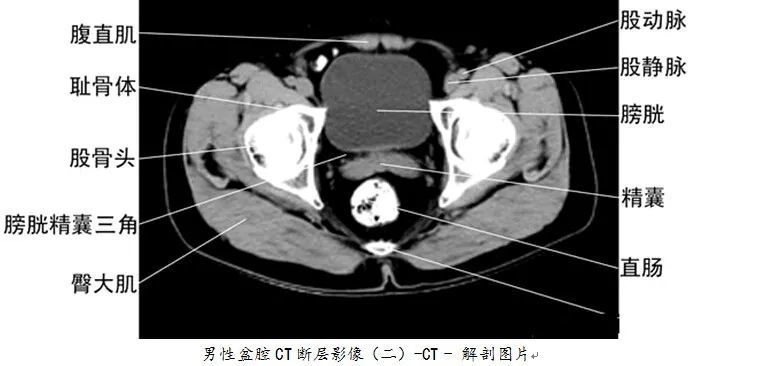

详细的全身ct图谱,赶紧收藏了吧!

【医科普】全身ct图谱,速收藏!

全身ct高清图谱建议收藏